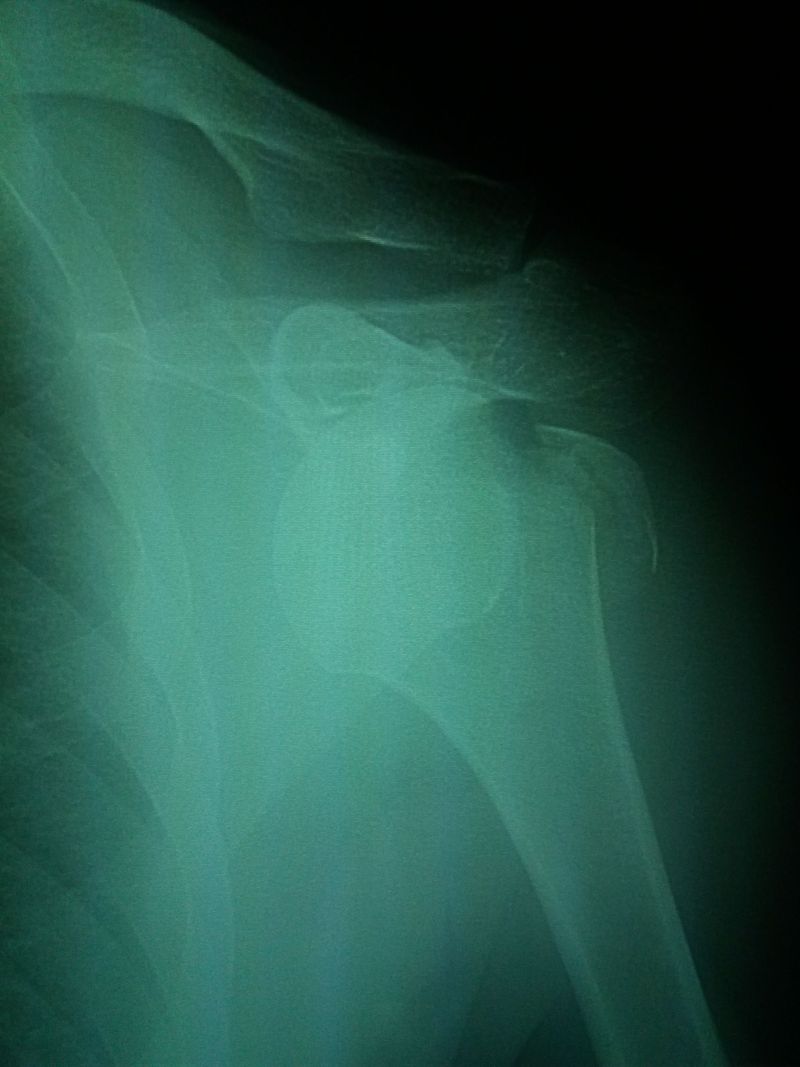

Bankarts lesion?

Anterior dislocation of the shoulder joint.

Anterior dislocation with greater tuberosity fracture

looks like a dislocation